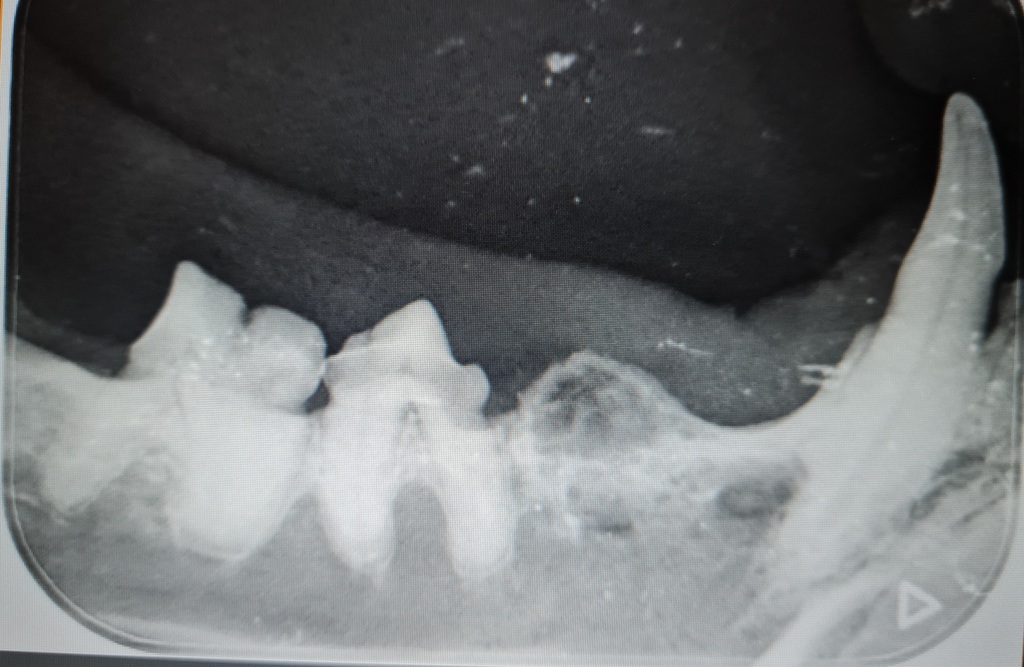

- das Dentalröntgen zur Abklärung dieser Patienten

Die Voraussetzung für eine gute Therapie dieser Tiere, ist eine gute und genaue Diagnostik. Hierfür kann man auf das intraorale Dentalröntgen nicht verzichten. Die meisten krankhaften Veränderungen befinden sich im äußerlich nicht sichtbaren Bereich der Zahnwurzel und des Zahnhalses und können nur durch bildgebende Verfahren sichtbar gemacht werden.